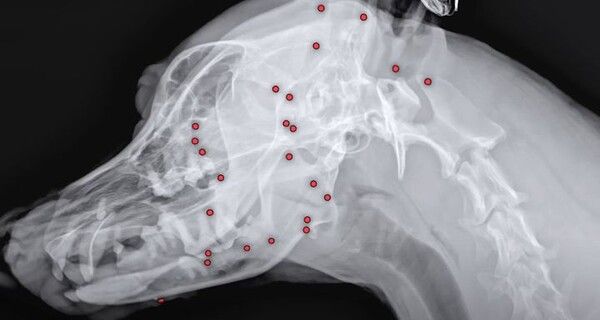

구조 당시 백구의 겉모습으로는 총알 자국을 확인할 수 없었다. 그러나 해외 입양을 앞두고 건강검진을 위해 찍은 엑스레이에서 산탄총 파편이 확인됐다. 이로 인해 백구의 입양은 무산됐고, 동물병원은 즉시 CT(컴퓨터 단층촬영) 등 정밀 검사에 들어갔다.

검사 결과, 총알은 머리부터 어깨, 가슴통, 엉덩이, 다리까지 온몸에 퍼져 있었다. 수술은 3시간 넘게 이어졌지만, 단 한 번의 수술로 파편을 전부 제거하는 것은 불가능했다. 수술이 장기간에 걸쳐 진행될 경우 방사선 피폭 위험이 컸고, 깊은 곳에 박힌 총알을 제거하다 장기가 손상될 수도 있기 때문이다. 더욱이 백구는 8~9세로 추정되는 노견이었다.

결국 의료진은 백구의 얼굴 위주로 총 26개의 파편만 제거할 수 있었다.